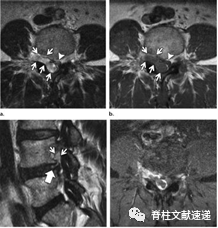

图注:49岁男性,极外侧腰椎间盘突出症。

大多数腰椎间盘突出症发生在椎管内,只有约7%-10%发生在椎间孔内或椎间孔外。椎间孔外椎间盘突出通常接近椎间孔的出口,约20%的椎间孔外椎间盘突出完全位于椎间孔外侧。

L4/5最常见。在极少数病例中,突出可以发生在神经鞘内,类似于良性或恶性的神经鞘肿瘤。

当临床腰椎间盘突出影像学责任节段与症状体征不一致时,需要考虑是否存在极外侧型腰椎间盘突出。